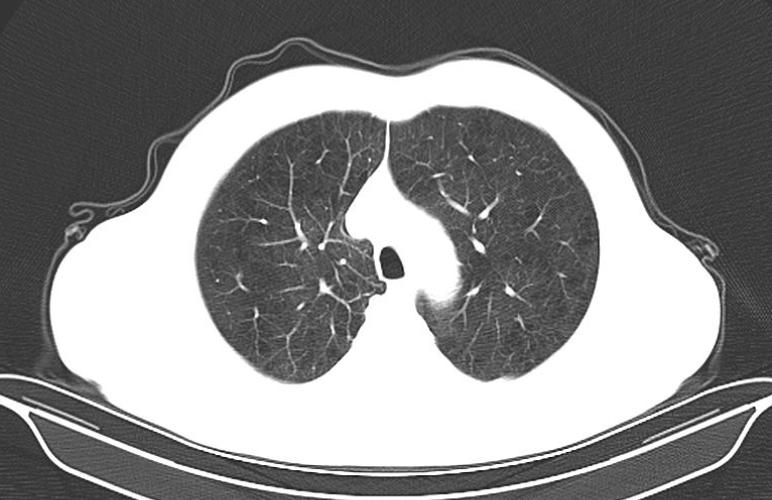

白色粗线就是条索

条索,在CT图像上形态类似条索状样的高密度影,说的通俗点,CT图像上的线状或者粗条状的白影就是条索。它是如何形成的呢?通常是由于成纤维细胞增生,导致纤维化,说的简单点,是因为之前肺部有炎症,现在已经痊愈,条索就是愈合后遗留下来疤痕。所以说,CT报告单上有少许条索,不必过于紧张。当然,肺间质纤维化患者会出现双肺多发粗大的条索,肺结核和一些肺部肿瘤的周边也会有条索的出现,因为这些病变同样会刺激成纤维细胞的增生,出现条索。